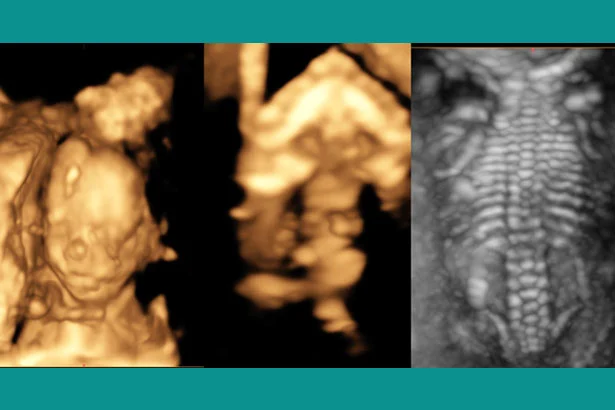

Our expert, Dr. Neha Gupta, is a highly qualified fetal medicine specialist. She has many years of experience in doing ultrasounds during pregnancy. She is not only trained in detection of abnormalities in the unborn child but will also counsel you how to approach further in the pregnancy. She is experienced in counseling the families in whom the future pregnancies (the unborn child) are at risk of developing hereditary diseases or helping those women who have some medical disorders which can affect the baby in the womb.